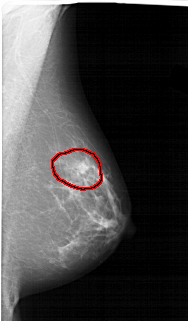

FILE: A_1456_1.RIGHT_MLO.OVERLAY

TOTAL_ABNORMALITIES 1

ABNORMALITY 1

LESION_TYPE MASS SHAPE IRREGULAR MARGINS ILL_DEFINED

ASSESSMENT 4

SUBTLETY 2

PATHOLOGY BENIGN

TOTAL_OUTLINES 1

BOUNDARY